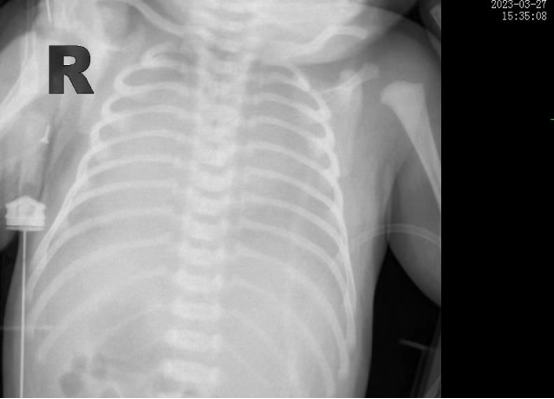

時間追溯到3月27日,該患兒出生時哭聲欠連貫,全身可見黃色胎糞附著,羊水三度污染,呼吸稍促,血氧飽和度低,立即轉(zhuǎn)入新生兒科。醫(yī)生立即予以清理呼吸道,常壓給氧,建立靜脈通道后抱入暖箱復溫,同時以無創(chuàng)輔助通氣。然而患兒呼吸窘迫癥狀正在進行性加重,胸片提示“白肺”,結(jié)合血氣分析等檢查后,患兒被診斷為“急性呼吸窘迫綜合癥”、“呼吸衰竭”。時間就是生命,主管醫(yī)生張海嬌在與家屬充分溝通同時,副主任醫(yī)師鐘玉芬立即帶領(lǐng)新生兒醫(yī)護團隊快速采取急救措施,給予患兒氣管插管術(shù)進行有創(chuàng)呼吸機高頻震蕩通氣,并從氣管內(nèi)滴入PS(肺表面活性物質(zhì)),以降低肺泡表面張力,增加肺順應性,患兒血氧這才穩(wěn)定下來。

在科室團隊的共同努力下,患兒歷經(jīng)5天有創(chuàng)通氣5天無創(chuàng)通氣,再調(diào)整為5天吸氧后已經(jīng)實現(xiàn)呼吸自由,復查肺部CT,終于看到白肺已云開霧散。4月15日,歷時17天的醫(yī)療救治,患兒順利出院,回到了媽媽的懷抱。

據(jù)悉,新生兒急性呼吸窘迫綜合征(ARDS)是一種嚴重威脅新生兒生命的呼吸危重癥,其主要臨床表現(xiàn)為不同程度的低氧血癥,雙肺彌漫性透光度下降,炎性滲出伴肺順應性下降。根據(jù)國際新生兒ARDS多中心研究中期報告,新生兒ARDS病死率大約為20%,而早期識別,進行良好的肺復張,預防及治療肺動脈高壓、心臟衰竭、液體管理及積極抗感染等綜合治療以降低病死率。